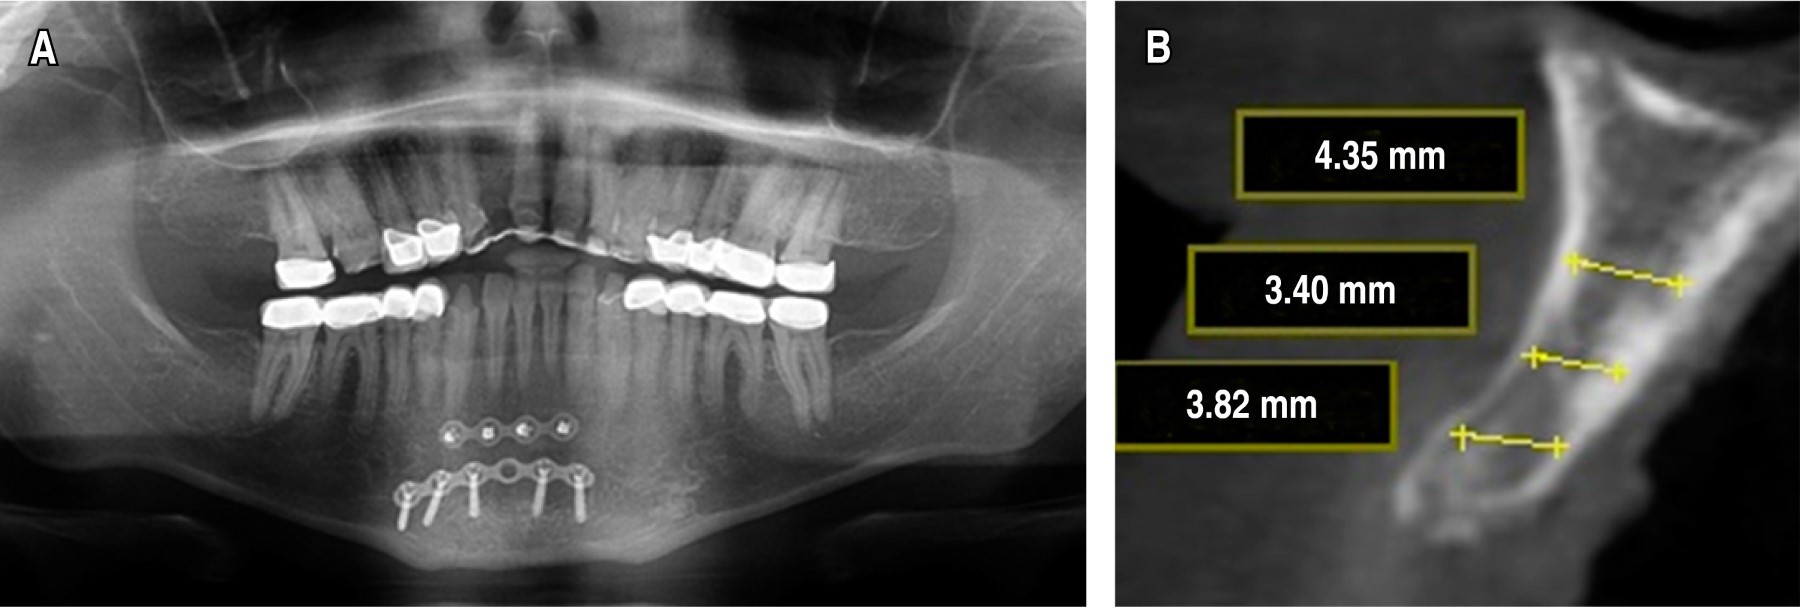

En el examen clínico y radiográfico, mediante una ortopantomografía, se evidenció ausencia del OD 12 (Figura 2A). Se solicitó estudio tipo Cone Beam, donde se observó en corte transaxial deficiencia de tejido óseo en sentido vestíbulo-palatino (Figura 2B), por lo que se estableció como diagnóstico deformidad del reborde alveolar anterior grado I Seibert y se estableció el mismo plan de tratamiento del caso 1, en una primera fase, toma de injerto autólogo en bloque del mentón y, posteriormente, en una segunda fase, la colocación del implante dental en zona del OD 12.

COLOCACIóN DEL IMPLANTE DENTAL

En la segunda fase quirúrgica, posterior a cinco meses, se solicitó a los pacientes tomografía Cone Beam para control postoperatorio, donde fue evidente una ganancia ósea en sentido horizontal de 2 a 5 mm aproximadamente en comparación con la deficiencia inicial (Figura 4A-D), los pacientes fueron llevados nuevamente a mesa operatoria bajo anestesia local, previa antisepsia del campo operatorio, se infiltró lidocaína al 2% más epinefrina 1:100,000 para bloqueo del nervio alveolar anterior, se abordó la zona con una incisión supracrestal con descargas laterales sin incluir papilas, se hizo levantamiento de colgajo mucoperióstico a espesor total, exponiendo la zona receptora y evidenciando clínicamente la completa integración del injerto a la zona receptora (Figura 5A), se procedió a retirar el material de osteosíntesis y a colocar el implante dental en la zona (Figura 5B y C), de forma satisfactoria y sin complicaciones, posteriormente, se realizó el control postquirúrgico del implante dental y se observó el mismo en posición y cubierto de hueso en su periferia (Figura 6).